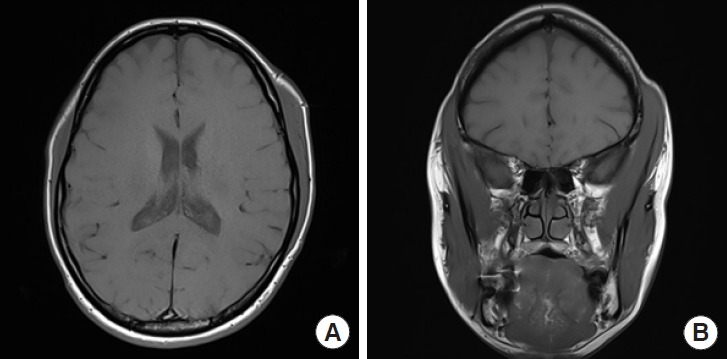

The initial instance of isolated unilateral temporalis muscle hypertrophy (IUTMH) was reported in 1990. Since then, only few cases have been documented. The cause of this condition remains ambiguous; however, it is presumed to be linked to compensatory and stress-induced hypertrophy. We introduce a rare case of the diagnosis and treatment of IUTMH. A 39-year-old woman presented with a steadily enlarging pain-free swelling on the left side of her face, first noticed a month ago. Apart from a hyperthyroidism medication regimen her medical history was unremarkable. She had no history of temporomandibular joint disease, bruxism, surgery, or trauma. However, she complained of having been under substantial stress lately. Contrast-enhanced magnetic resonance imaging revealed asymmetric temporalis muscle hypertrophy. The treatment plan consisted of administering type A botulinum toxin injections into left temporalis muscle, supplemented by lifestyle changes and relaxation techniques. At a follow-up visit 9 months after the injections, the muscle contour was normalized both in physical and in radiologic examinations. While further supportive evidence is needed, it can be anticipated that cosmetic treatment with botulinum toxin, rather than surgical interventions, will become the standard treatment of IUTMH.